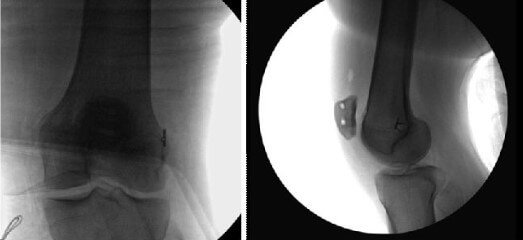

Un factor determinant al succesului reconstructiei MPFL il constituie fixarea corespunzatoare a grefei in femur, tehnica noastra incorporand folosirea unui template femural pentru a asigura plasarea corespunzatoare a grefei in femur. Aceasta pozitie asigura un punct de fixare static care egalizeaza tensiunea de-a lungul grefei, atat in flexie, cat si in extensie, minimizand astfel stresul asupra articulatiei patelo-femurale. Cu ajutorul unui template MPFL se stabileste pozitia adecvata a brosei. Punctul de insertie (entry point) se afla la aproximativ 1 mm anterior de linia de extensie a cortexului posterior, la 2,5 mm distal de marginea articulara posterioara a condilului femural medial, si proximal de nivelul punctului posterior al liniei lui Blumensaat. Template-ul se pozitioneaa pe aria epicondilului medial al femurului, unde cu ajutorul brosei ghid se realizeaza un canal de 2,4 mm, de-a lungul femurului si prin epicondilul lateral. Din moment ce diametrul grefei de muschi gracillis are un diametru de aproximativ 4-5 mm, se alezeaza cu un alezor de 6 mm.

Reconstructia ligamentului femuro-patelar medial

Se plaseaza un fir ghid Nitinol de 1.1 mm langa ghidul femural pentru a facilita insertia surubului de bio-interferenta de 6 mm x 23 mm. Se introduc firele de sutura ale grefei in capsa unei brose Kirschner si se petrec prin femurul lateral, anterior introducerii grefei in priza femurala. Folosind o pensa ca scripete, se pre-tensioneaza grefa si se insereaza in canal cu tensiune egala pe ambele capete ale grefei. Se fixeaza manual fateta rotuliana laterala la acelasi nivel cu condilul femural lateral, cu genunchiul in flexie de 30 de grade. In acest moment al timpului operator, este posibila evaluarea provizorie a izometriei grefei prin mentinerea unei tensiuni adecvate a grefei si prin executarea miscarilor complete ale genunchiului. Odata ce a fost stabilita izometria propice a grefei, poate fi realizata fixarea completa. In timp ce se tensioneaza grefa, se insereaza surubul de 6 mm in femur (nota: se evalueaza traseul si laxitatea rotulei de-a lungul anvergurii miscarilor genunchiului. Daca sunt necesare unele ajustari, se scoate surubul, se stabilesc tensiunile sau pozitionarile necesare si se reinsereaza surubul).